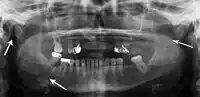

Panoramic radiography

Panoramic radiographs are tomograms where the mandible is in the focal trough and show a flat image of the mandible. Because the curve of the mandible appears in a 2-dimensional image, fractures are easier to spot leading to an accuracy similar to CT except in the condyle region. In addition, broken, missing or malaligned teeth can often be appreciated on a panoramic image which is frequently lost in plain films. Medial/lateral displacement of the fracture segments and especially the condyle are difficult to gauge so the view is sometimes augmented with plain film radiography or computed tomography for more complex mandible fractures.

Panoramic radiograph of a simple mandible fracture of the right mandibular body, minimally displaced. Note that the teeth to the left of the fracture do not touch